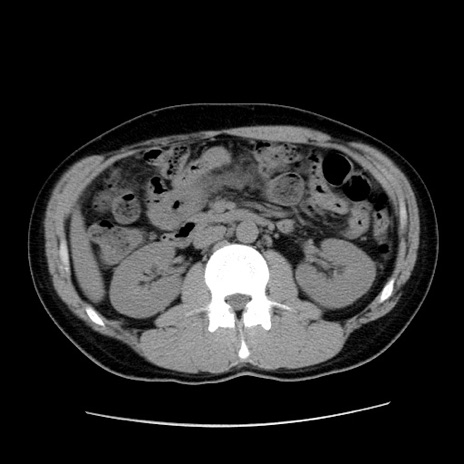

症例36(横断像)

【症例】20歳代 男性

【主訴】心窩部痛

【現病歴】今朝より上腹部痛あり。一旦軽快していたが再度出現したため救急要請。昨日夕に白身の魚を含む刺身を食べた。

【身体所見】BP 136/89mmHg、HR 74/min、BT 37.0℃、腹部:膨満、軟、心窩部に圧痛あり。反跳痛なし、筋性防御なし、腸雑音やや亢進あり。

【データ】WBC 17700、CRP 0.48